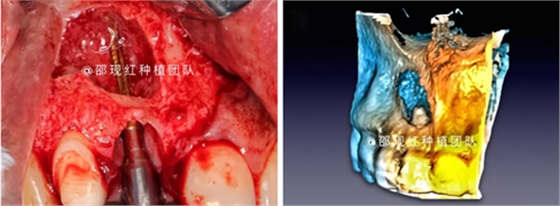

CASE ONE

11 12雙根尖聯(lián)合囊腫病例

術(shù)中使用科盧森骨粉

植骨術(shù)后9個月成骨情況